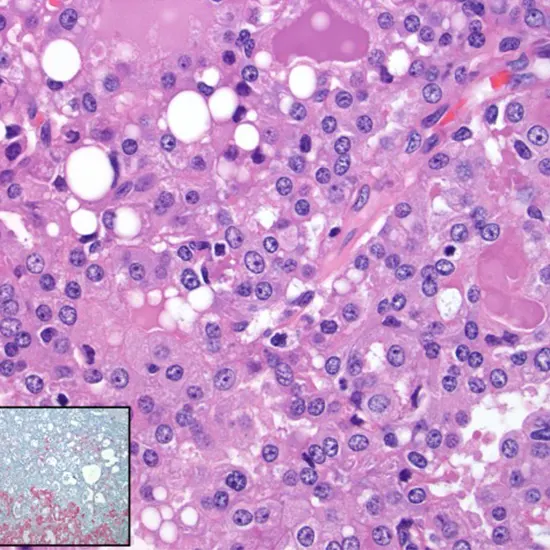

Diagnosis of MSC typically involves a combination of physical examination, imaging tests (such as mammography, ultrasound, or MRI), and biopsy to confirm the presence of MSC cells. MSC is typically characterized by the presence of characteristic microscopic features, including secretory cells with abundant eosinophilic cytoplasm (meaning they stain pink under a microscope) and the presence of secretory material.